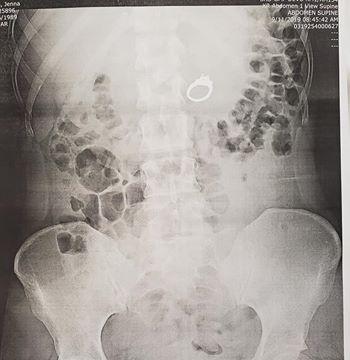

Vị trí của chiếc nhẫn trong cơ thể cô gái

Các bác sĩ tìm thấy chiếc nhẫn đính hôn trong ruột của Evans ở ngay phía trên vùng bụng. Evans cho biết chồng chưa cưới đã trả lại chiếc nhẫn cho cô vào thứ năm.